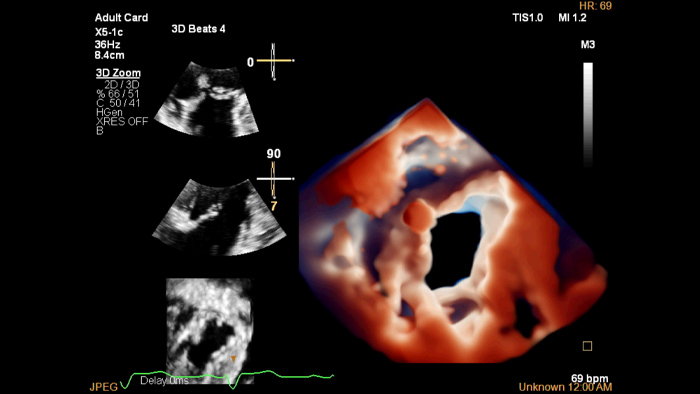

EPIQ CVx

The EPIQ CVx is a dedicated cardiac ultrasound solution which brings significant advancements in functionality. This helps you deliver better care through higher processing power, exceptional imaging with more clarity & sharpness, improved exam efficiencies, complemented by the proven, robust quantification capabilities of Ultrasound Workspace.